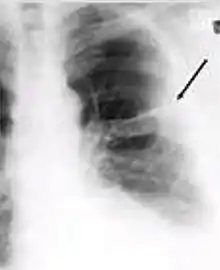

Dense homogenous opacity in right, middle and lower lobe of primary pulmonary TB.

Chest x-ray showing patchy opacification on the upper right and mid-zone lung with fibrotic shadows, as well as bilateral hilar lymphadenopathy.

Chest x-ray showing coarse reticulonodular densities on the lower right lung of post-primary pulmonary TB.

Chest x-ray of Ghon's complex of active tuberculosis